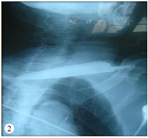

急诊行颈部X线片检查以明确金属利器所处位置及颈部组织损伤情况。X线片结果示左颈部刀刺伤伴金属异物(图2)。急诊血常规检验示红细胞2.89×1012/L,血红蛋白88 g/L,红细胞压积26%,血小板138×109/L,中性粒细胞7.2×109/L。